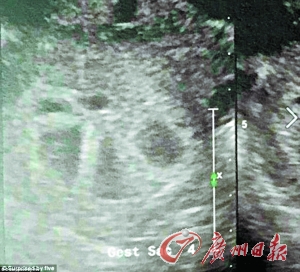

产检时,医生发现有5个独立的心脏在跳动。

塔奇夫妇来到医院做检查,医生认为她怀了双胞胎。然而,当她要求使用另一个超音波机器来更清晰地观看胎儿时,医生意外发现有5个独立的心脏在跳动。原来,她怀的居然是5胞胎,一共有4个女孩和一个男孩。